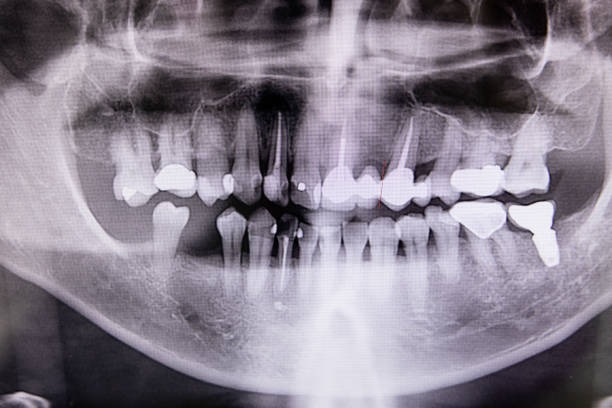

Radiographie Rétro-Alvéolaire

La radiographie rétro-alvéolaire est un examen précis permettant de visualiser la dent dans sa totalité, y compris la racine et l’os environnant.